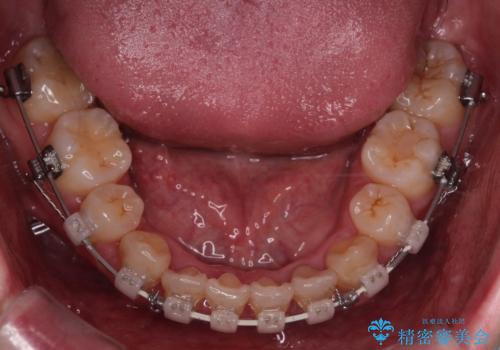

- 矯正装置

- 審美装置

難しいケースでしたが、矯正用アンカースクリューを用いながら、臼歯関係もきれいに仕上げることができました。